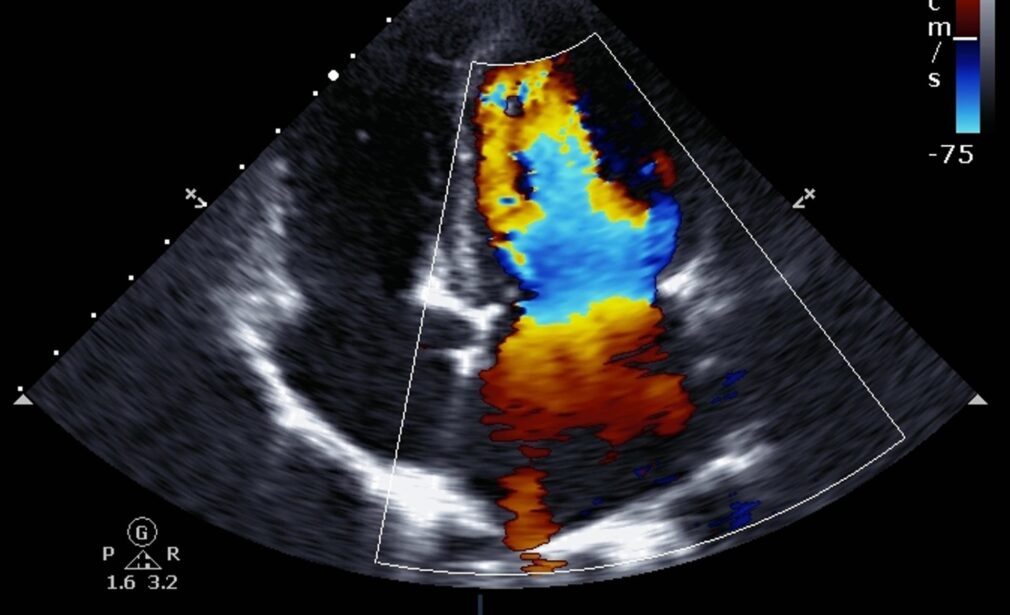

A Trans-Esophageal Echocardiogram is an advanced form of echocardiography where a flexible probe with an ultrasound transducer is passed down the esophagus to obtain detailed images of the heart. Since the esophagus lies close to the heart, TEE produces clearer, high-resolution images compared to standard echocardiograms.

A Bubble Echo is a specialized form of echocardiography where saline microbubbles are injected into the bloodstream to detect abnormal blood flow between the heart chambers.

Real-time ultrasound detects bubbles crossing between heart chambers